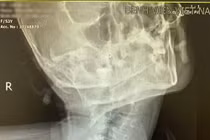

Kíp gây mê – hồi sức Bệnh viện Việt Nam – Thụy Điển Uông Bí vừa thực hiện thành công một ca đặt nội khí quản khó cho người bệnh N.T.L. (53 tuổi, trú tại Bình Khê – Quảng Ninh) có tình trạng vẹo, xoắn cột sống cổ lâu năm.

Đây là ca lâm sàng phức tạp do biến dạng giải phẫu vùng cổ gây hạn chế nghiêm trọng khả năng ngửa đầu và quan sát thanh môn, làm tăng nguy cơ thất bại khi đặt nội khí quản bằng phương pháp thông thường.